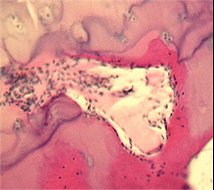

Pathological changes seen in human arthritis are associated with reported pain sensation. We are investigating the possible relationships between joint pathology and pain focusing on two models of OA. Modern quantitative methods of molecular biology and histology are used to explore how changes in the joint accompany changes in pain processing and pain behaviour. Interventional studies that inhibit innervation at the osteochondral junction, reduce synovitis and modify OA structural severity are being studied to determine their ability to modify pain behaviour. We are investigating how treatments that improve arthritis in the joint may reduce pain behaviour even after discontinuation of treatment.